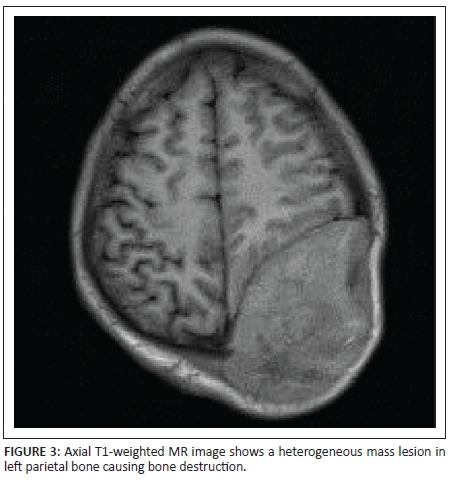

X-rays of the skull showed a well-defined lytic lesion in the left parietal bone with an associated large soft tissue component. No marginal sclerosis or periosteal reaction was noted (Figure 1a and 1b). Non-contrast computed tomography (NCCT) revealed a well-defined heterogeneous hyperdense mass lesion centred on the left parietal bone causing bone destruction, compressing the adjacent brain parenchyma and bulging into the scalp. A few small bony fragments were seen at the periphery of the lesion (Figure 2). Magnetic resonance imaging (MRI) of the brain with contrast demonstrated a well-defined heterogeneously enhancing soft tissue mass lesion measuring 8.0 cm × 7.9 cm × 6.8 cm causing destruction of the left parietal bone and bulging into the scalp. Some flow voids were seen with the mass. No restricted diffusion or surrounding oedema was noted. There was mass effect with compression of adjacent brain parenchyma and mild midline shift to the right side. The mass was compressing adjacent superior sagittal sinus but not invading it (Figures 3, 4, 5 and 6). Skeletal survey of the body revealed no other lytic lesions anywhere in the body.

On radiography, SPB presents as a well-defined osteolytic lesion with clear margins and narrow zone of transition. There is no bony sclerosis or periosteal reaction. The lesion is hyperdense on NCCT and shows marked homogenous enhancement with contrast. Small bony fragments may be seen at the periphery. On MRI, SPB appears isointense on T1-weighted images and hyperintense on T2-weighted images. Intratumoural flow voids have been described. The lesion shows dense but heterogeneous enhancement with contrast.3,5,6